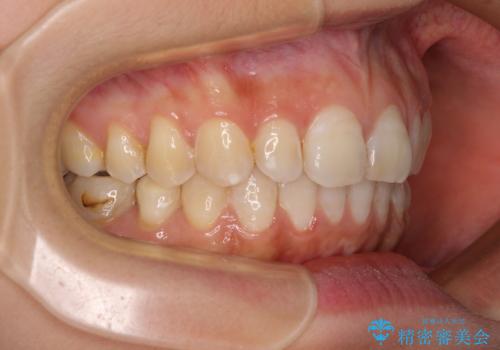

- 下顎の前歯が隠れていることと、デコボコを気にして来院された患者様です。

目立ちにくい装置を希望されていたため、ワイヤー装置とインビザラインを提案したところ、インビザラインを希望されました。

銀歯やムシ歯処置の必要な歯が奥歯にあり気になっていたので、矯正治療の途中でセラミッククラウンへ変更し、その後歯列を仕上げていくこととしました。